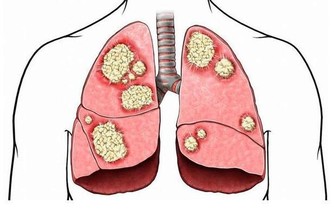

萬萬沒想到吧。抽煙不僅僅傷害肺部,而且能直接損傷胃粘膜,損害胃的微血管,使胃黏膜長期處於缺氧狀態,最終導致慢性胃炎的發生。